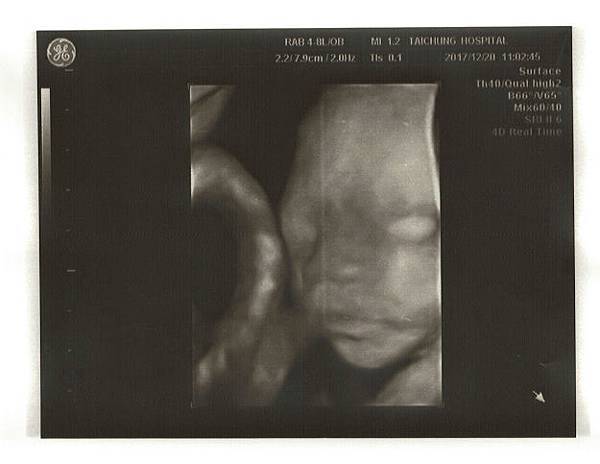

接著照超音波,這次直接照腹部超音波就看得清楚了,寶寶長大了,脊椎看得好清楚,雙手還揮來揮去的,太可愛了~!

醫生說他的姿勢像個小沙彌,在揮手、吃手~Chris在旁邊看了笑得好開心。

心跳147下,身高7.67cm,都在標準值喔!寶寶好棒~!